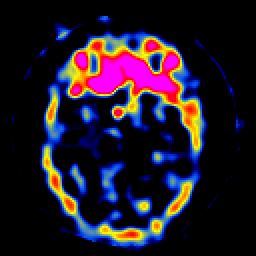

SPECT TL Study #8 -- Slice #19

[Home][Help][Clinical][Tour 1][Tour 2][Tour 3] Slice 19